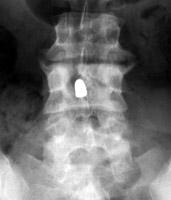

Tumbling Bullet Sign

Post traumatic bone cyst

Two sets of frontal and lateral radiographs, separated only by time, which reveal the "tumbling bullet sign"--which is simply a bullet which changes its location and orientation within a solitary bone cyst. This sign serves two purposes. It is documentation of the evolution of a solitary bone cyst as a corollary of trauma, and reveals the free movement of the foreign body within the confines of the lesion establishing its cystic rather than solid nature. It is similar to the fallen fragment sign.

- Click on the image for a larger versionA - Click on the image for a larger versionB - Click on the image for a larger versionC - Click on the image for a larger versionD